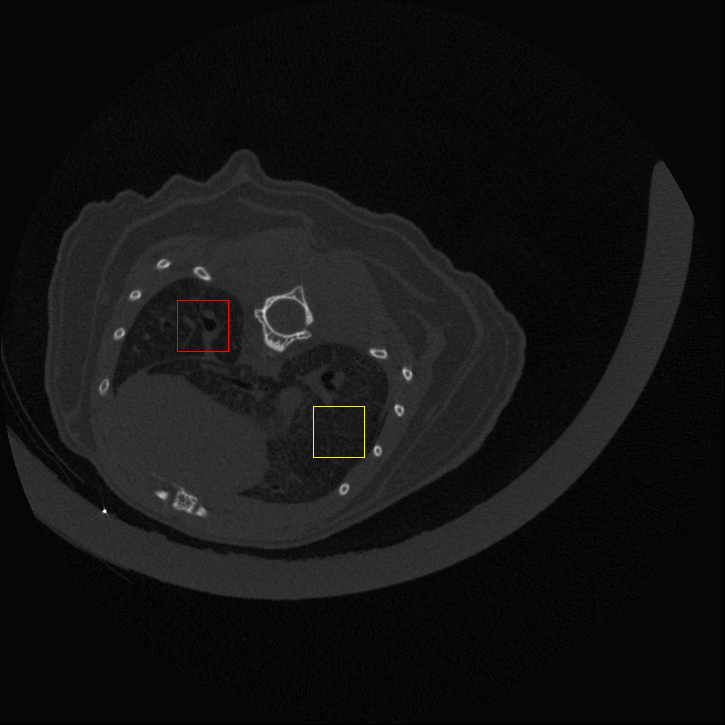

Figure 4: Visual comparsion of SRCT Case 111 from the Tibia dataset. The restored bony structures are shown in the red and yellow boxes in Fig. 5. The display window is [-900, 2000] HU.

Figure 5: Zoomed regions of interest (ROIs) marked by the red rectangle in Fig. 4. The restored image with GAN-CIRCLE reveals subtle structures better than the other variations of the proposed neural network, especially in the marked regions. The display window is [-900, 2000] HU.

III-D Experimental Results with the Tibia Dataset

We evaluated the proposed algorithms against the state-of-the-art algorithms on the tibia dataset. We present typical results in Fig. 4. It is observed that BM3D can effectively remove the noise, but it over-smoothens the noisy LR images. Then, the interpolation-based methods (NN+, Bilinear+, Bicubic+, Lanczos+) yield noticeable artifacts caused by partial aliasing. On the other hand, the DL-based methods suppress such artifacts effectively. It can be seen that our proposed GAN-CIRCLE recovers more fine subtle details and captures more anatomical information in Fig. 5. It is worth mentioning that Fig. 4 shows that there are severe distortions of the original images but SRGAN generates compelling results in Figs. 6-8, which indicate VGG network is a task-specific network which can generate images with excellent image quality. We argue that the possible reason is that the VGG network [68] is a pre-trained CNN-based network based on natural images with structural characteristic correlated with the content of medical images [80]. Fig. 5 presents that the proposed GAN-CIRCLEs can predict images with shaper boundaries and richer textures than GAN-CIRCLE, and GAN-CIRCLEu which learns additional anatomical information from the unpaired samples. The quantitative results are in Table II. The results demonstrate that the G-Forward achieves the highest scores using the evaluation metrics, PSNR and SSIM, which outperforms all other methods. However, it has been pointed out in [81, 82] that high PSNR and SSIM values cannot guarantee a visually favorable result. Non-GAN based methods (FSRCNN, ESPCN, LapSRN) may fail to recover some fine structure for diagnostic evaluation, such as shown by zoomed boxes in Fig. 5. Quantitatively, GAN-CIRCLE achieves the second best values in terms of SSIM and IFC. It has been pointed out in [83] that IFC value is correlated well with the human perception of SR images. Our GAN-CIRCLEs obtained comparable results qualitatively and quantitatively. Table II shows that the proposed semi-supervised method performs similarly compared to the fully supervised methods on the tibia dataset. In general, our proposed GAN-CIRCLE can generate more pleasant results with sharper image contents.